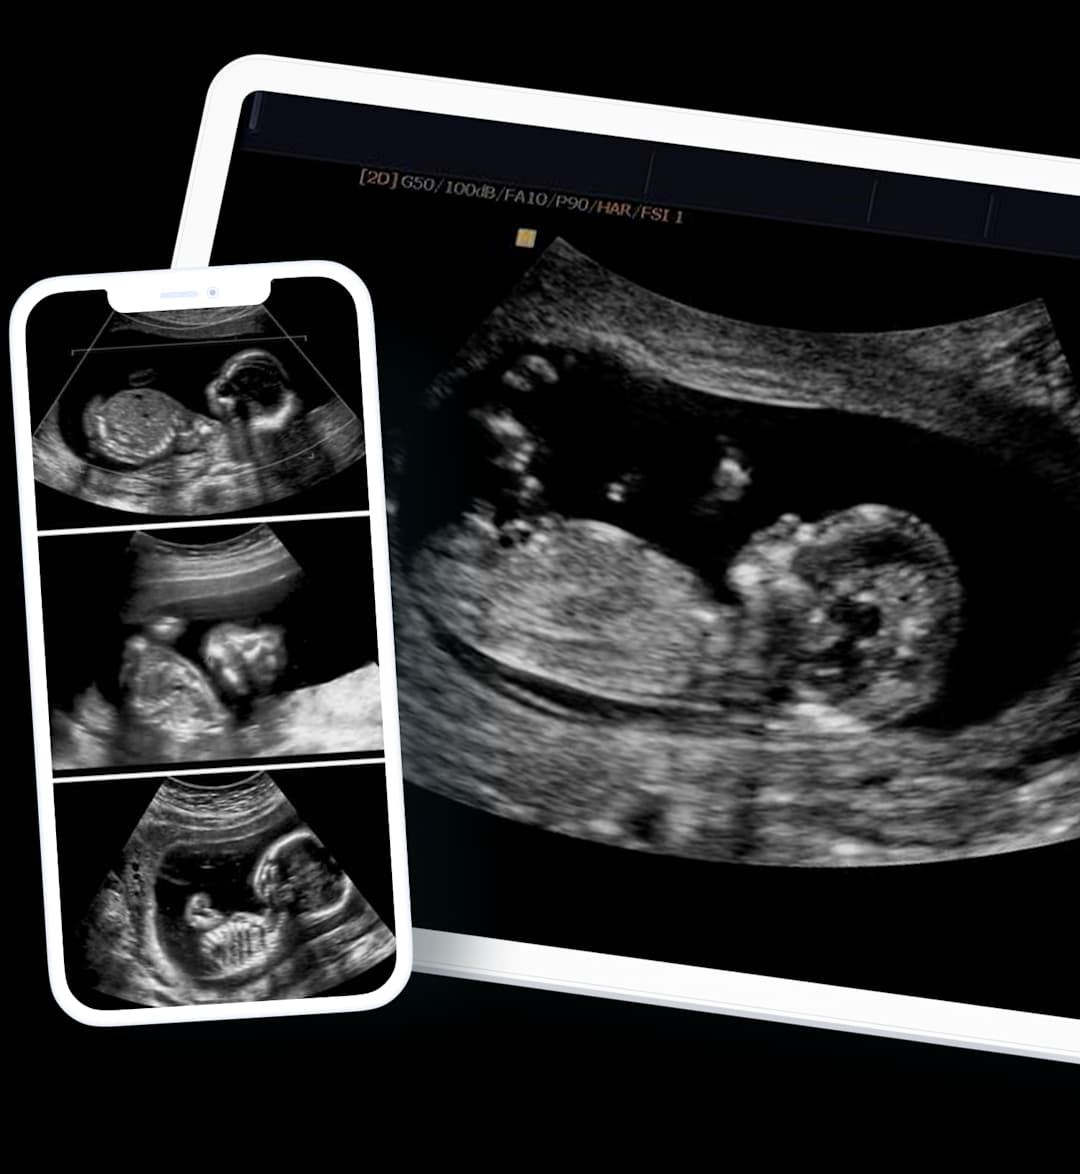

An Early Pregnancy Ultrasound is a scan performed shortly after finding out you are pregnant. Usually, 6 to 10 weeks after conception and the purpose of the scan is to confirm the pregnancy, assess early viability and provide an approximate date of the pregnancy.

In addition to the report, images of your scan will be sent for you to share with a healthcare specialist of your choice.

We can provide scan images directly to your smartphone, often on the same day following your appointment. Gain the peace of mind and insight you need, without delay.